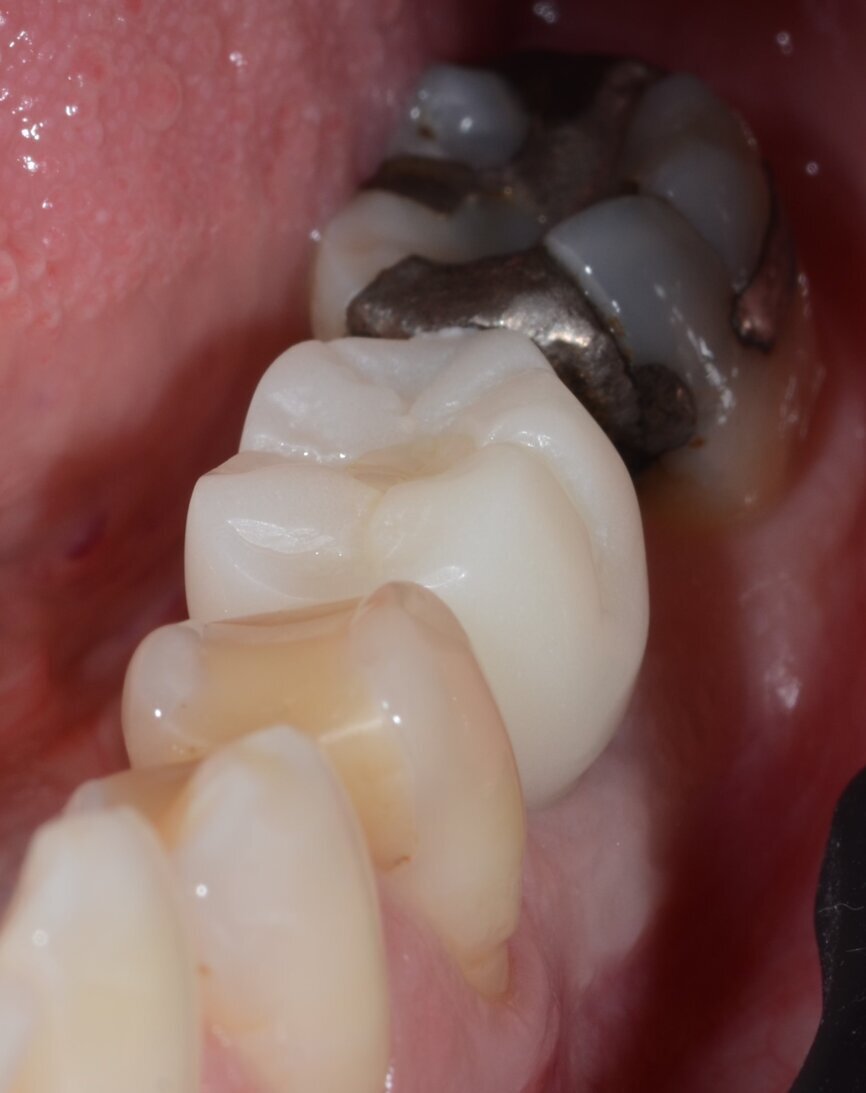

The patient, a 67-year-old non-smoking man without any relevant medical history, was referred to the office with a missing tooth (#36) due to persistent apical periodontitis. The tooth had been extracted more than one year prior to the procedure and the molar site was well maintained and fully healed (Fig. 1). A CBCT scan showed that the patient had favourable bone availability (Fig. 2), on which basis a one-stage placement of a 5.5 × 10.0 mm Straumann BLX implant was planned. After surgically installing the implant (Figs. 3–7), Salvesen allowed the surrounding soft tissue to mature and heal for six weeks (Fig. 8). He then removed the healing abutment to begin the prosthetic procedures for a temporary crown (Figs. 9 & 10). A stone master cast was made in the laboratory, and a temporary screw-retained PMMA crown was manufactured over a Straumann wide base temporary abutment for the crown (Fig. 11) and placed on to the implant (Figs. 12–14).

Fig. 2: CBCT scan measurements demonstrate availability of bone of adequate height and width.